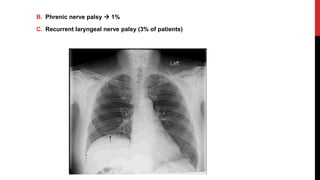

B. Phrenic nerve palsy  1%

C. Recurrent laryngeal nerve palsy (3% of patients)